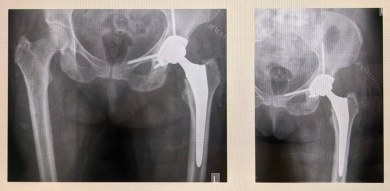

В отделение травматологии и ортопедии МОНИКИ поступила женщина с сильными болями в тазобедренном суставе. Ранее он уже был оперирован из-за коксартроза – заболевания, приводящего к деформации суставной щели и ограничивающего подвижность сустава.

Обследование выявило в вертлужной впадине костный дефект – расшатывание компонента эндопротеза, установленного ранее.

«Мы удалили старый эндопротез и провели санацию с установкой временного эндопротеза с антибиотиком, купировав воспаление. Затем удалили временный эндопротеза и сделали повторное эндопротезирование сустава с установкой укрепляющей конструкции и костной пластикой дефекта вертлужной впадины. Учитывая сложную конфигурацию дефекта, была рассчитана и выполнена индивидуальная укрепляющая конструкция посредством применения 3D-принтинга. Такой метод применяется для пациентов с застарелыми повреждениями и посттравматическими костными дефектами», – рассказал заведующий отделением травматологии и ортопедии МОНИКИ Евгений Степанов.